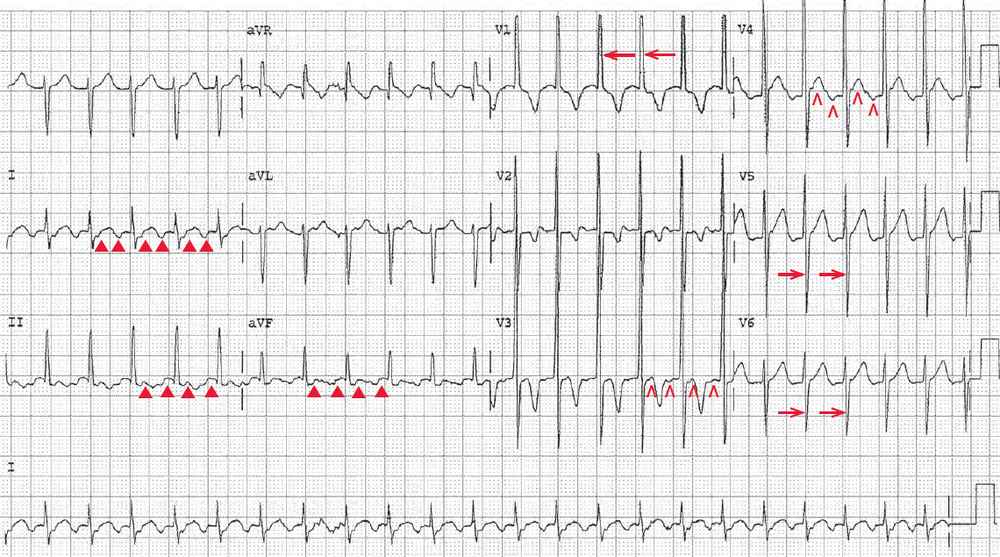

Several minutes after presentation, the heart rate abruptly slowed to 140 bpm, and another ECG was obtained.

There is a regular rhythm with a rate of 140 bpm. Although there are no distinct P waves, there are typical atrial flutter waves (at a rate of 280 bpm) seen, primarily in leads II, III, and aVF (▲). They may also be seen in leads V3–V4 (^). Hence this rhythm is atrial flutter with 2:1 AV block. The atrial rate is identical to the ventricular rate in the previous ECG, confirming that this was indeed atrial flutter with 1:1 AV conduction.

There is a tall R wave in lead V1 (←) and a deep S wave in leads V5–V6 (→), with an S/R ratio > 1. The tall R wave in V1 and the deep S wave in leads V5–V6 are characteristic for right ventricular hypertrophy; this accounts for the rightward axis. Although the nature of the congenital heart disease is not certain, it was most certainly associated with right ventricular volume or pressure load, and most likely due to left to right shunting.